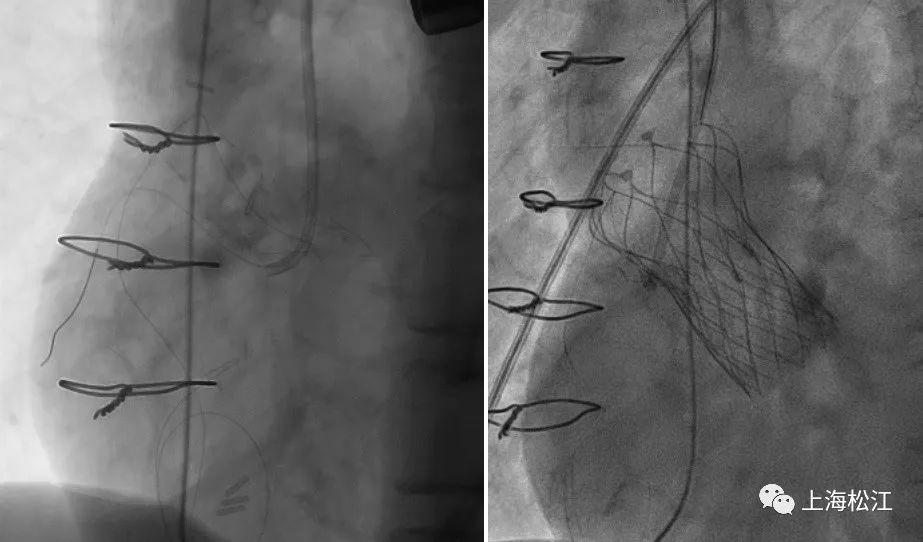

11月12日上午,手术进行。考虑该患者的右冠状动脉开口较低,首先由心内科李旭光操作,在右冠状动脉内留置了保护导丝及鞘管以备不测。随后,由叶一舟、施盛等团队成员经双侧股动脉做穿刺置管,成功建立了跨越主动脉瓣通往左心室的手术路径,在DSA影像和食道超声的辅助下,装载着瓣膜支架的输送系统缓慢送至预定释放位置,通过与麻醉医师的起搏配合,成功在主动脉瓣位植入瓣膜支架一枚。

手术后,医生们即刻通过超声及DSA造影确认:人工主动脉瓣膜开闭正常,无瓣周漏,无传导阻滞,冠脉血流通畅。术后患者返回ICU病房即刻拔除气管插管,意识清楚,术后第二日即下床活动,手术取得圆满成功。